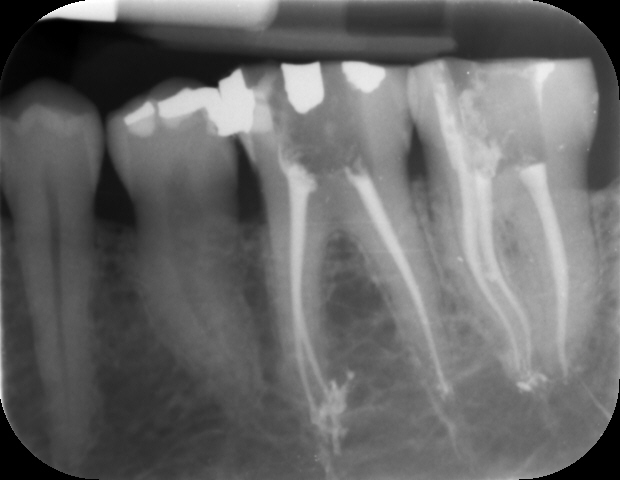

La radiografia endorale è un esame di radiologia odontoiatrica che permette al dentista di avere informazioni dettagliate ma circoscritte ad uno od, al massimo, 3 denti il tutto su una lastra di piccole dimensioni (detta anche lastrina endorale). La parola “endorale” sta a significare che la lastrina che riceve le radiazioni ionizzate viene posta all’interno della bocca del paziente (endo = dentro), generalmente sorretta da uno sostegno in plastica mantenuto in sede dal morso. Come si effettua? La procedura per eseguire una radiografia endorale è molto semplice: il dentista prepara la lastra ricevente e la sistema nel cavo orale del paziente il quale ha il compito di tenerla ferma serrando i denti e mordendo un supporto di plastica a cui la lastrina stessa è connessa. Le dimensioni dalla radiografia endorale sono molto ridotte (in media 30 mm x 40 mm) e questo permette di diminuire al massimo il disagio per il paziente. Per mezzo di un cono lungo e centratori che hanno il compito di circoscrivere la porzione di arcata interessata dall’esame, l’apparecchio viene appoggiato alla guancia del paziente il quale è protetto dall’irradiamento attraverso una mantella o grembiule piombato e/o da un collare per evitare che le radiazioni possano colpire la tiroide, organo molto sensibile. Il tempo di esposizione è simile a quello di una normale fotografia, tutto si conclude in centesimi di secondo e la radiografia compare immediatamente sullo schermo del computer.